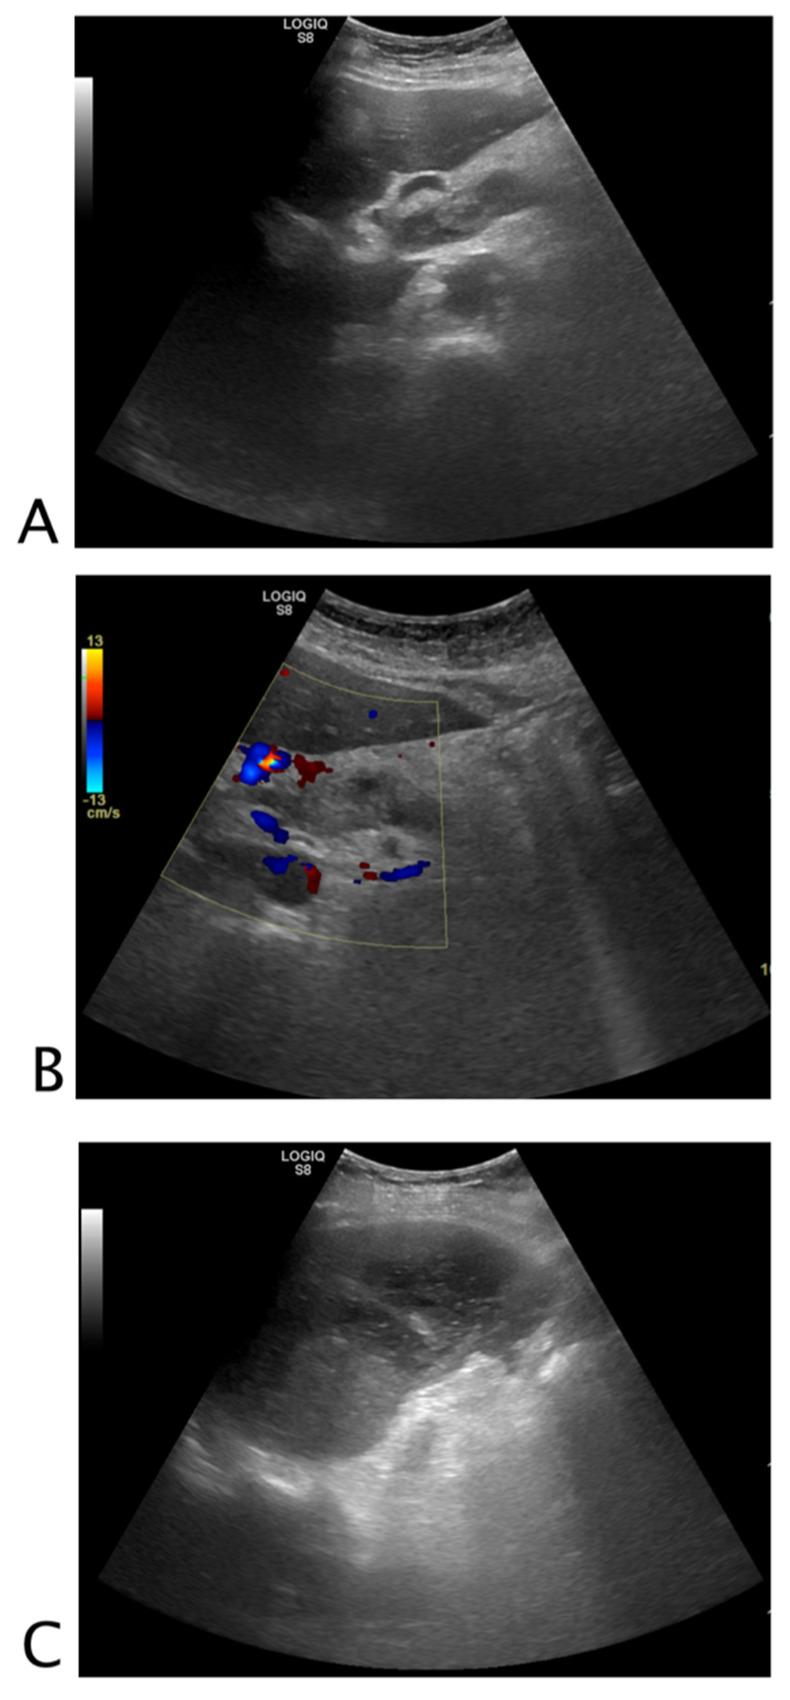

A key issue in abdominal US is the assessment of fluid, which is usually anechoic, thus appearing "black". Our approach focuses on searching for fluid in non-traumatic patients, providing a new, simplified method for point-of-care US (POCUS).

Fluid assessment is based on a three-step analysis that we can thus summarize. 1. Look for black where it should not be. This means searching for effusions or collections. 2. Check if black is too much. This means evaluating anatomical landmarks where fluid should normally be present but may be abnormally abundant. 3. Look for black that is not clearly black. This means evaluating fluid aspects, whether wholly anechoic or not (suggesting heterogeneous or corpusculated fluid).

腹部超声检查中的一个关键问题是对液体的评估,液体通常是无回声的,因此呈现“黑色”。我们的方法专注于在非创伤性患者中寻找液体,为床旁超声检查(POCUS)提供了一种新的、简化的方法。

液体评估基于我们可以总结的三步分析。1. 在不该出现黑色的地方寻找黑色。这意味着寻找积液或液性聚集。2. 检查黑色是否过多。这意味着评估正常情况下应该有液体但可能异常增多的解剖标志。3. 寻找并非明显黑色的黑色。这意味着评估液体的特征,无论是否完全无回声(提示液体不均匀或有细胞成分)。